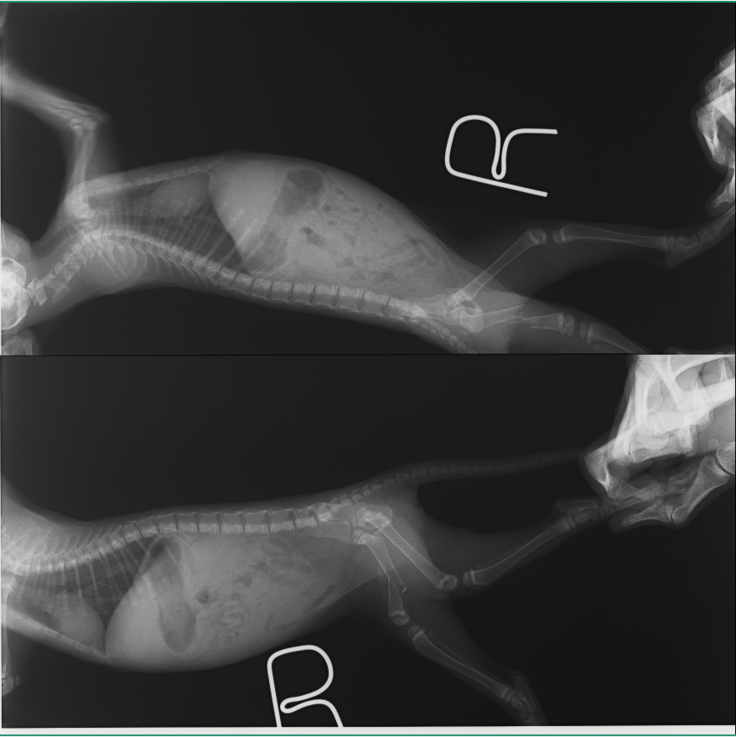

レントゲンにあるように

複雑な骨折になっており、細かい骨も周りに散らばり

靭帯が損傷し膝の可動域が現在ない状態で曲がらない。

という状態でした。

まずはレントゲンの写真をご覧ください

6月17日でのレントゲンです

固着してきてますが、骨の欠片が飛び出ているようになっています。

そして抜糸当日の24日

完全に固着していないものの、飛び出した骨も安定してきており

先生の判断で抜糸という経緯になりました。